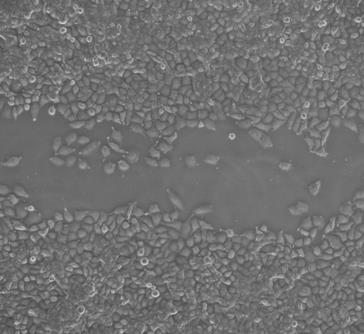

細(xì)胞劃痕實(shí)驗(yàn)|專注醫(yī)學(xué)科研外包

細(xì)胞劃痕是一種簡(jiǎn)單易行的檢測(cè)細(xì)胞運(yùn)動(dòng)的方法,實(shí)驗(yàn)成本低,可以用來(lái)檢測(cè)貼壁生長(zhǎng)腫瘤細(xì)胞的侵襲轉(zhuǎn)移能力。

細(xì)胞劃痕實(shí)驗(yàn)服務(wù)